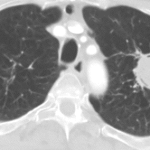

Patient with haemoptysis

Patient coughing up large amount of blood. 66 year patient with cavitating left lung lesion likely mycetoma and haemoptysis. CT scan...